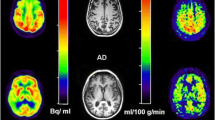

To examine CMRglc measures and corresponding glucose transport (K 1 and k 2) and phosphorylation (k 3) rates in the medial temporal lobe (MTL, comprising the hippocampus and amygdala) and posterior cingulate cortex (PCC) in mild Alzheimer’s disease (AD).

Dynamic FDG PET with arterial blood sampling was performed in seven mild AD patients (age 68 ± 8 years, four females, median MMSE 23) and six normal (NL) elderly (age 69 ± 9 years, three females, median MMSE 30). Absolute CMRglc (μmol/100 g/min) was calculated from MRI-defined regions of interest using multiparametric analysis with individually fitted kinetic rate constants, Gjedde-Patlak plot, and Sokoloff’s autoradiographic method with population-based rate constants. Relative ROI/pons CMRglc (unitless) was also examined.

With all methods, AD patients showed significant CMRglc reductions in the hippocampus and PCC, and a trend towards reduced parietotemporal CMRglc, as compared with NL. Significant k 3 reductions were found in the hippocampus, PCC and amygdala. K 1 reductions were restricted to the hippocampus. Relative CMRglc had the largest effect sizes in separating AD from NL. However, the magnitude of CMRglc reductions was 1.2- to 1.9-fold greater with absolute than with relative measures.

CMRglc reductions are most prominent in the MTL and PCC in mild AD, as detected with both absolute and relative CMRglc measures. Results are discussed in terms of clinical and pharmaceutical applicability.